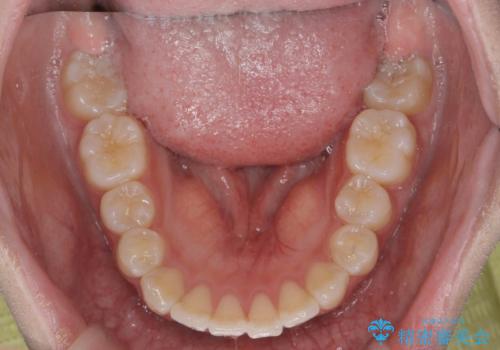

- 他院での矯正治療中に行かなくなってしまい、装置をつけたまま矯正治療の続きを希望され来院されました。

マウスピースでは並べることが難しい左下の奥歯を部分ワイヤー矯正で並べたのち、マウスピース矯正装置インビザラインで歯並びを整えていきます。